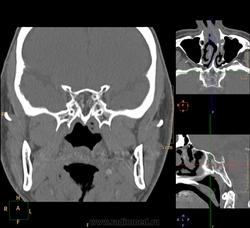

Одна пазуха: